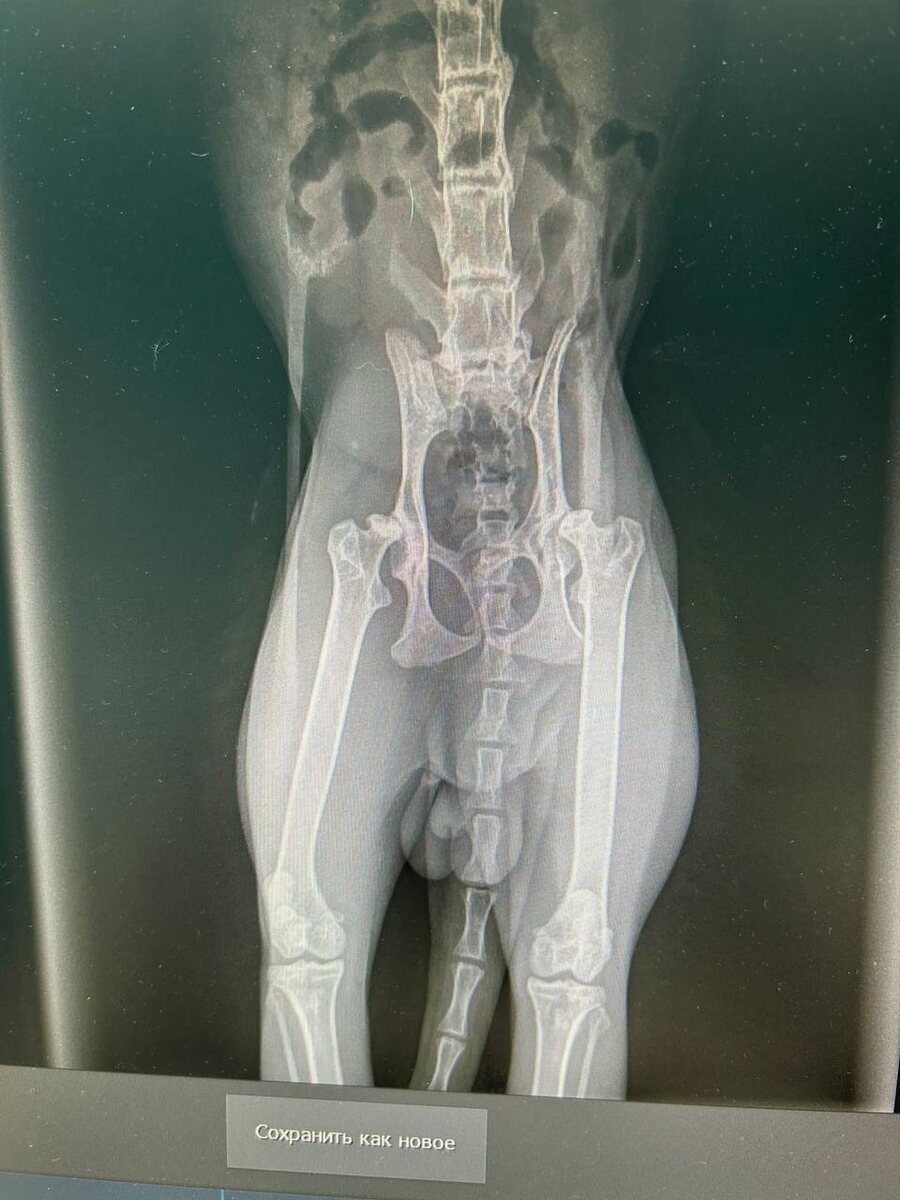

Котику Мите предстоят как минимум ТРИ операции! - удаление зубов и санация пасти - оба тазобедренные суставы ( в два подхода) - кастрация ————————- Коту реально больно ходить из за неправильного срастания перелома таза ! Поэтому скорее всего будут операции , но не за раз , а за два раза! Так же ему больно кушать из за десен и плохих зубов! У котика КАЛЬЦЕВИРОС- начали лечение, снимут воспаление и только тогда будет санация пасти и удаление плохих зубов! Суммы за операции будут большие, и оплата стационара каждые сутки ! Без вашей помощи никак не осилить все это , очередной сложный котик! Но есть одна радость- у него нет таких инфекций, как иммунодефицит и лейкоз 🙏Слава Богу отрицательно Если вы хотите помочь , при переводе оставляйте комментарий⤵️ «БЛАГОТВОРИТЕЛЬНОСТЬ» Т- банк 2200701901051810 Райфайзен 2200300504041300 Сбербанк 4276550098163119 Все привязаны к номеру телефона +7(981)706-83-99 Петрова Анна Викторовна

Коту реально больно ходить из за неправильного срастания перелома таза !

Поэтому скорее всего будут операции , но не за раз , а за два раза!